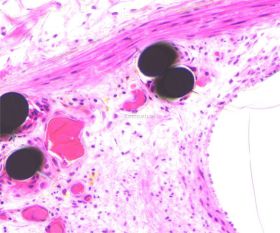

使用德国EXAKT切磨系统进行硬组织切片,特别是对于含有金属这类植入物的组织,是一种精确的组织切片技术。

将包埋好的硬组织树脂块,用EXAKT 硬组织切片机先切一个200um的厚片,然后再通过EXAKT 硬组织磨片机将其磨到20-30um薄片,样本是已经硬组织包埋好的含金属的动物样本。

针对不同的病理阅片指标需求,行HE染色、Masson染色、亚甲基蓝-酸性品红染色、VG染色、Movat染色等。